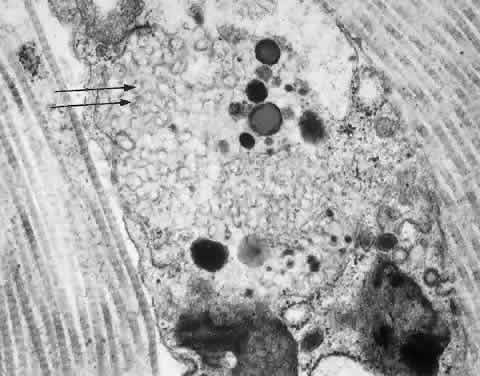

Histochemical and ultrastructural studies of the eye in MLD have been reported.199 The retinal ganglion cells contain a metachromatic complex that, on electron microscopy, appears to be formed of inclusion bodies with a laminated structure. Electron microscopic studies of the eyes of patients with different clinical and genetic variants of MLD have revealed profound demyelination and loss of axons in the optic nerve in all cases.198 A variety of membrane-bound inclusions are present in the cytoplasm of glial cells; some appear whorled, homogenous, and granular, whereas others have a lamellar or prismatic configuration.198,200 The varied ultrastructural appearance of the storage inclusions is explained by the progressive transformation of their content because the nonmetabolized sulfatide moiety of myelin becomes relatively more concentrated as the molecule undergoes catabolism. The final stage of this process is represented by the prismatic inclusions, which are believed to consist of sulfatide. Demyelination with intact axons is found in corneal and conjunctival nerves.